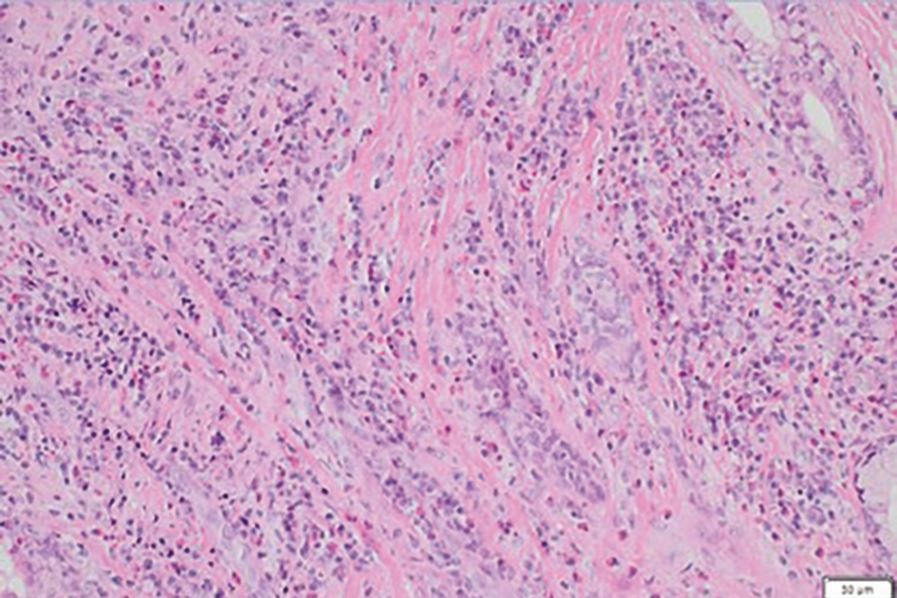

Histopathology of biopsy specimen from palatal tissue (report: non-specific inflammatory process, characterised by dense interstitial inflammatory infiltrate, no evidence of granulomas, and negative for syphilis, fungal infection, or Epstein-Barr virus. There was an increase in IgG4+ plasma cells, raising the suspicion of IgG4-related disease. The sample was negative for vasculitis, lymphoma, and malignancy)